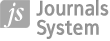

A well-known term: Krukenberg tumour, means a metastatic signet-ring cell adenocarcinoma of the ovary, often bilateral, originating from a gastrointestinal primary in 70% of cases, or from the breast and biliary tract [11] (Figure 1).

Figure 1

A 66-year-old woman with gastric carcinoma (poorly cohesive ca) after total gastrectomy with lymphadenectomy, postoperative chemoradiotherapy with 45 Gy radical radiotherapy to the gastric area and regional lymph nodes. Follow-up magnetic resonance imaging – Krukenberg tumours (arrows) confirmed after surgery: within the ovaries metastases of signet ring cell gastric cancer. Upper row: inhomogeneous abnormal ovaries on T2-weighted image (T2WI) (A), STIR (B) with inhomogeneous diffusion restriction (C). T1WI before (D) and after contrast medium administration (E, F) – very inhomogeneous contrast enhancement of the affected ovaries

While considering the metastatic character of ovarian lesions one must take into account synchronous endometrial and ovarian cancer (SEOC), which is a relatively rare entity with a better prognosis compared to metastatic malignancy of each organ (Figure 2).

Figure 2

A 52-year-old woman with the absurd suspicion of adenomyosis, put forward after ultrasound. Multiple tumours in the uterine body and cervix as well as in both ovaries. After surgery: synchronous G1 endometrioid carcinoma of the uterus and ovaries, most likely on the basis of endometriosis. The arrows point at the smaller lesion in the left ovary. A, B) T2WI, C) STIR, D-F) post-contrast T1WI

In the vagina, metastases account for as much as 80% of malignant tumours, and approximately two-thirds of those derive from cervical (mainly) and endometrial primary cancers [14] (Figure 3).

Figure 3

A 71-year-old woman with a diagnosis of endometrial carcinoma (A-D). Magnetic resonance imaging shows the additional findings: metastasis to the vagina (A, D-F, arrows) and to the right ovary (B, C). A, B, E) T2WI, C, D, F) post-contrast T1WI

Metastases to the uterus are rare and derive from breast, colon, stomach, pancreas, gallbladder, lung (Figure 4), cutaneous melanoma, urinary bladder, and thyroid [15].

Figure 4

A 54-year-old woman with adenocarcinoma of the left lung with known metastases in both lungs and adrenal glands. Magnetic resonance imaging (MRI) showed metastases to the uterine corpus (as a whole) and focally to the cervix (A, D), to the vagina on the left side (B, C, F), to the urinary bladder on the left side (A-D, F), and to the urethra (E). Bone metastases were also depicted on pelvic MRI (not shown here). A, B, E) T2WI, C) T1WI, D, F) post-contrast T1WI